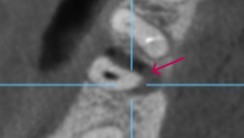

【CT画像 遠心根の近心側から舌側にかけて骨が消失 頬側骨は完全に消失しており歯根が露出している】

【赤矢印 骨消失部分】